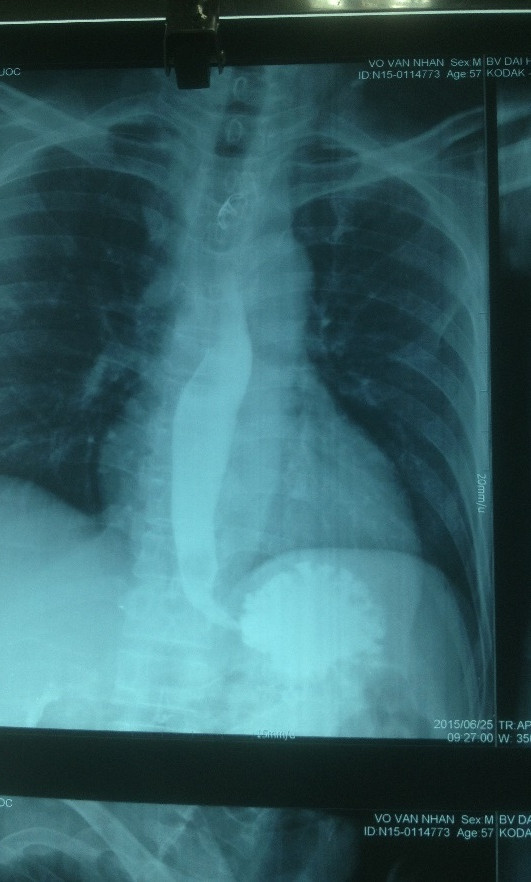

Hình X-quang kiểm tra thực quản sau phẫu thuật. Ảnh do bệnh viện cung cấp.

Kết quả chụp CT ngực của ông N. phát hiện có hiện tượng viêm trung thất kèm thủng thực quảng 1/3 trên do xương cá gây ra. Rất may vị trí xương cá ở xa cung động mạch chủ ngực của bệnh nhân. Ngay sau đó bệnh nhân được chỉ định nội soi dạ dày để gắp xương ra.